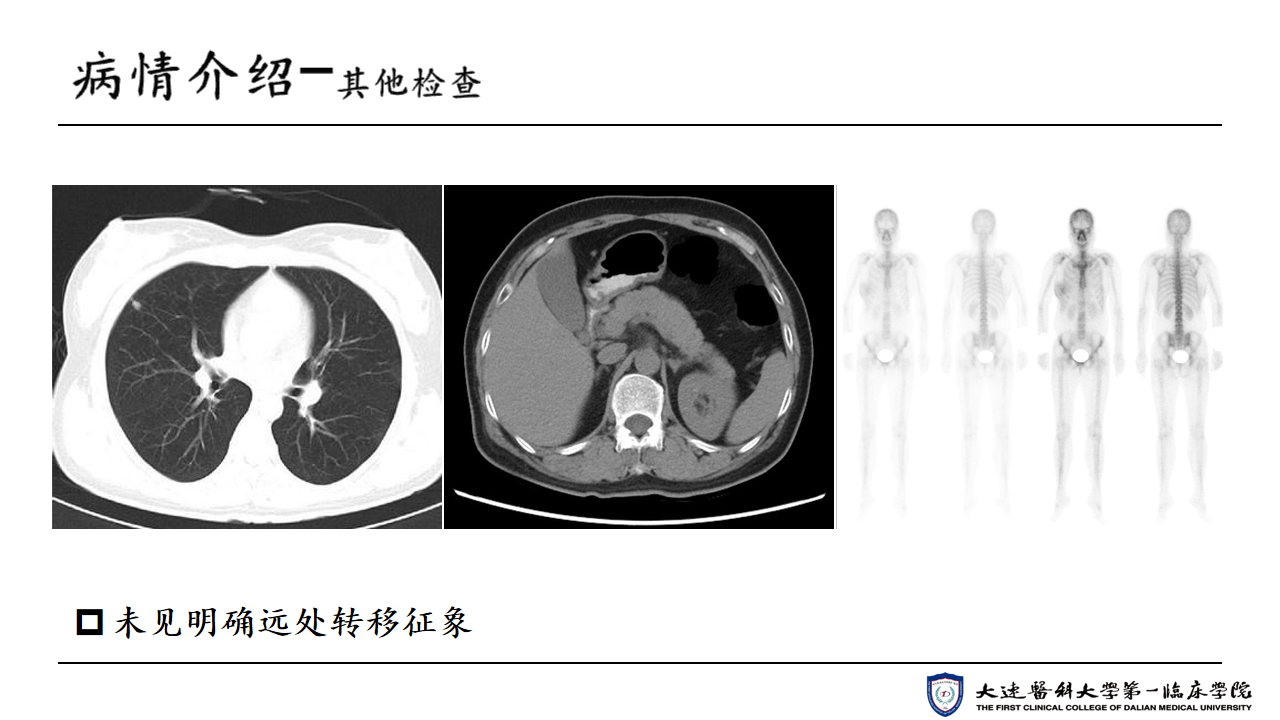

【35 under 35 ASCO放疗病例】王晓杰医生:Her-2阳性晚期乳腺癌病例

编译:王晓杰 大连医科大学附属第一医院